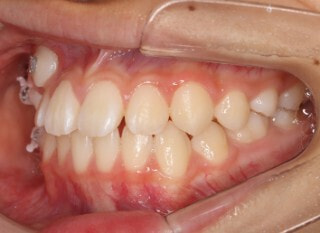

小児期の第二段階

終了時